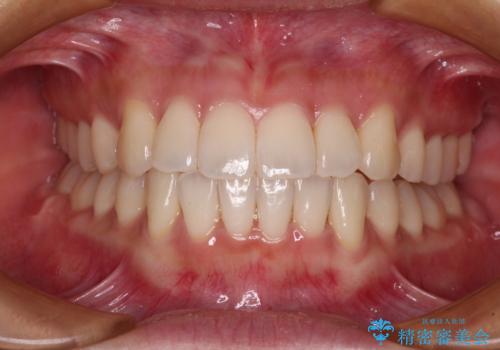

このような咬み合わせの場合、治療期間は2年以上がかかることが一般的で、3年程度かかることもありえるケースです。

強く深い咬み合わせにより下顎装置は頻繁に脱離するため、治療期間が長くなりますが、予定通りに終了させることができました。